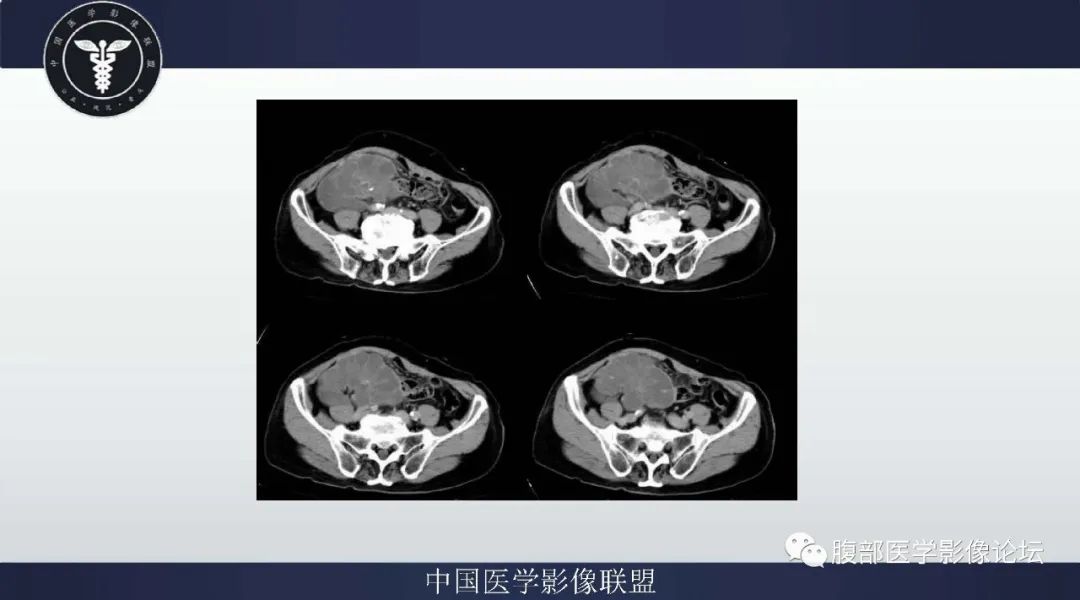

施彪:右下腹腔巨大不规则团块影,呈膨胀性生长,与肠系膜分界不清,增强后病灶渐进性延迟中度强化,内见分支状血管影,T1低信号,T2等高信号,条状、片状低密度/信号不强化区提示肿瘤内的间质黏液变性及纤维瘢痕可能,结合病史较长,老年男性,质硬(提示病灶内部纤维组织存在),首先考虑腹内型AF,鉴别 1.间质瘤: 大部分发生于肠道壁, 向内外生长, 易发生出血坏死, 增强明显强化, 以静脉期明显, 有时病灶内可见不规则肿瘤血管影; 2.肉瘤类(MFH、平滑肌肉瘤、纤维肉瘤):通常内有时可见低信号肌性纤维成分, 容易出血坏死,而AF的信号一般较其均匀, 无明显出血、坏死; 3.SFT: 病灶有包膜, 边界清楚锐利, 增强呈“快进慢出”强化方式, 内可见丰富肿瘤血管影; 4.淋巴瘤: 一般为多病灶融合, 轻中度强化, 程度较AF低, 且T2信号明显偏低, DWI信号较AF高, 局部血管包绕, 呈“血管漂浮”征; 5.转移瘤: 多有原发肿瘤病史, 一般多发, 坏死多见。

纳木错:右中下腹盆占位,与肠系膜,阑尾分界不清,T1低,T2高提示内含粘液,增强后实性部分、分隔及囊壁延迟强化,CEA升高,考虑来源于阑尾的黏液腺癌。

向前向后:病灶沿肠系膜包绕血管生长,囊性部分较多,边缘强化,定位应该是肠系膜粘液血管型不排除;淋巴瘤,包绕血管;粘液腺瘤做鉴别。 医学百科网 | YxBaike.Com